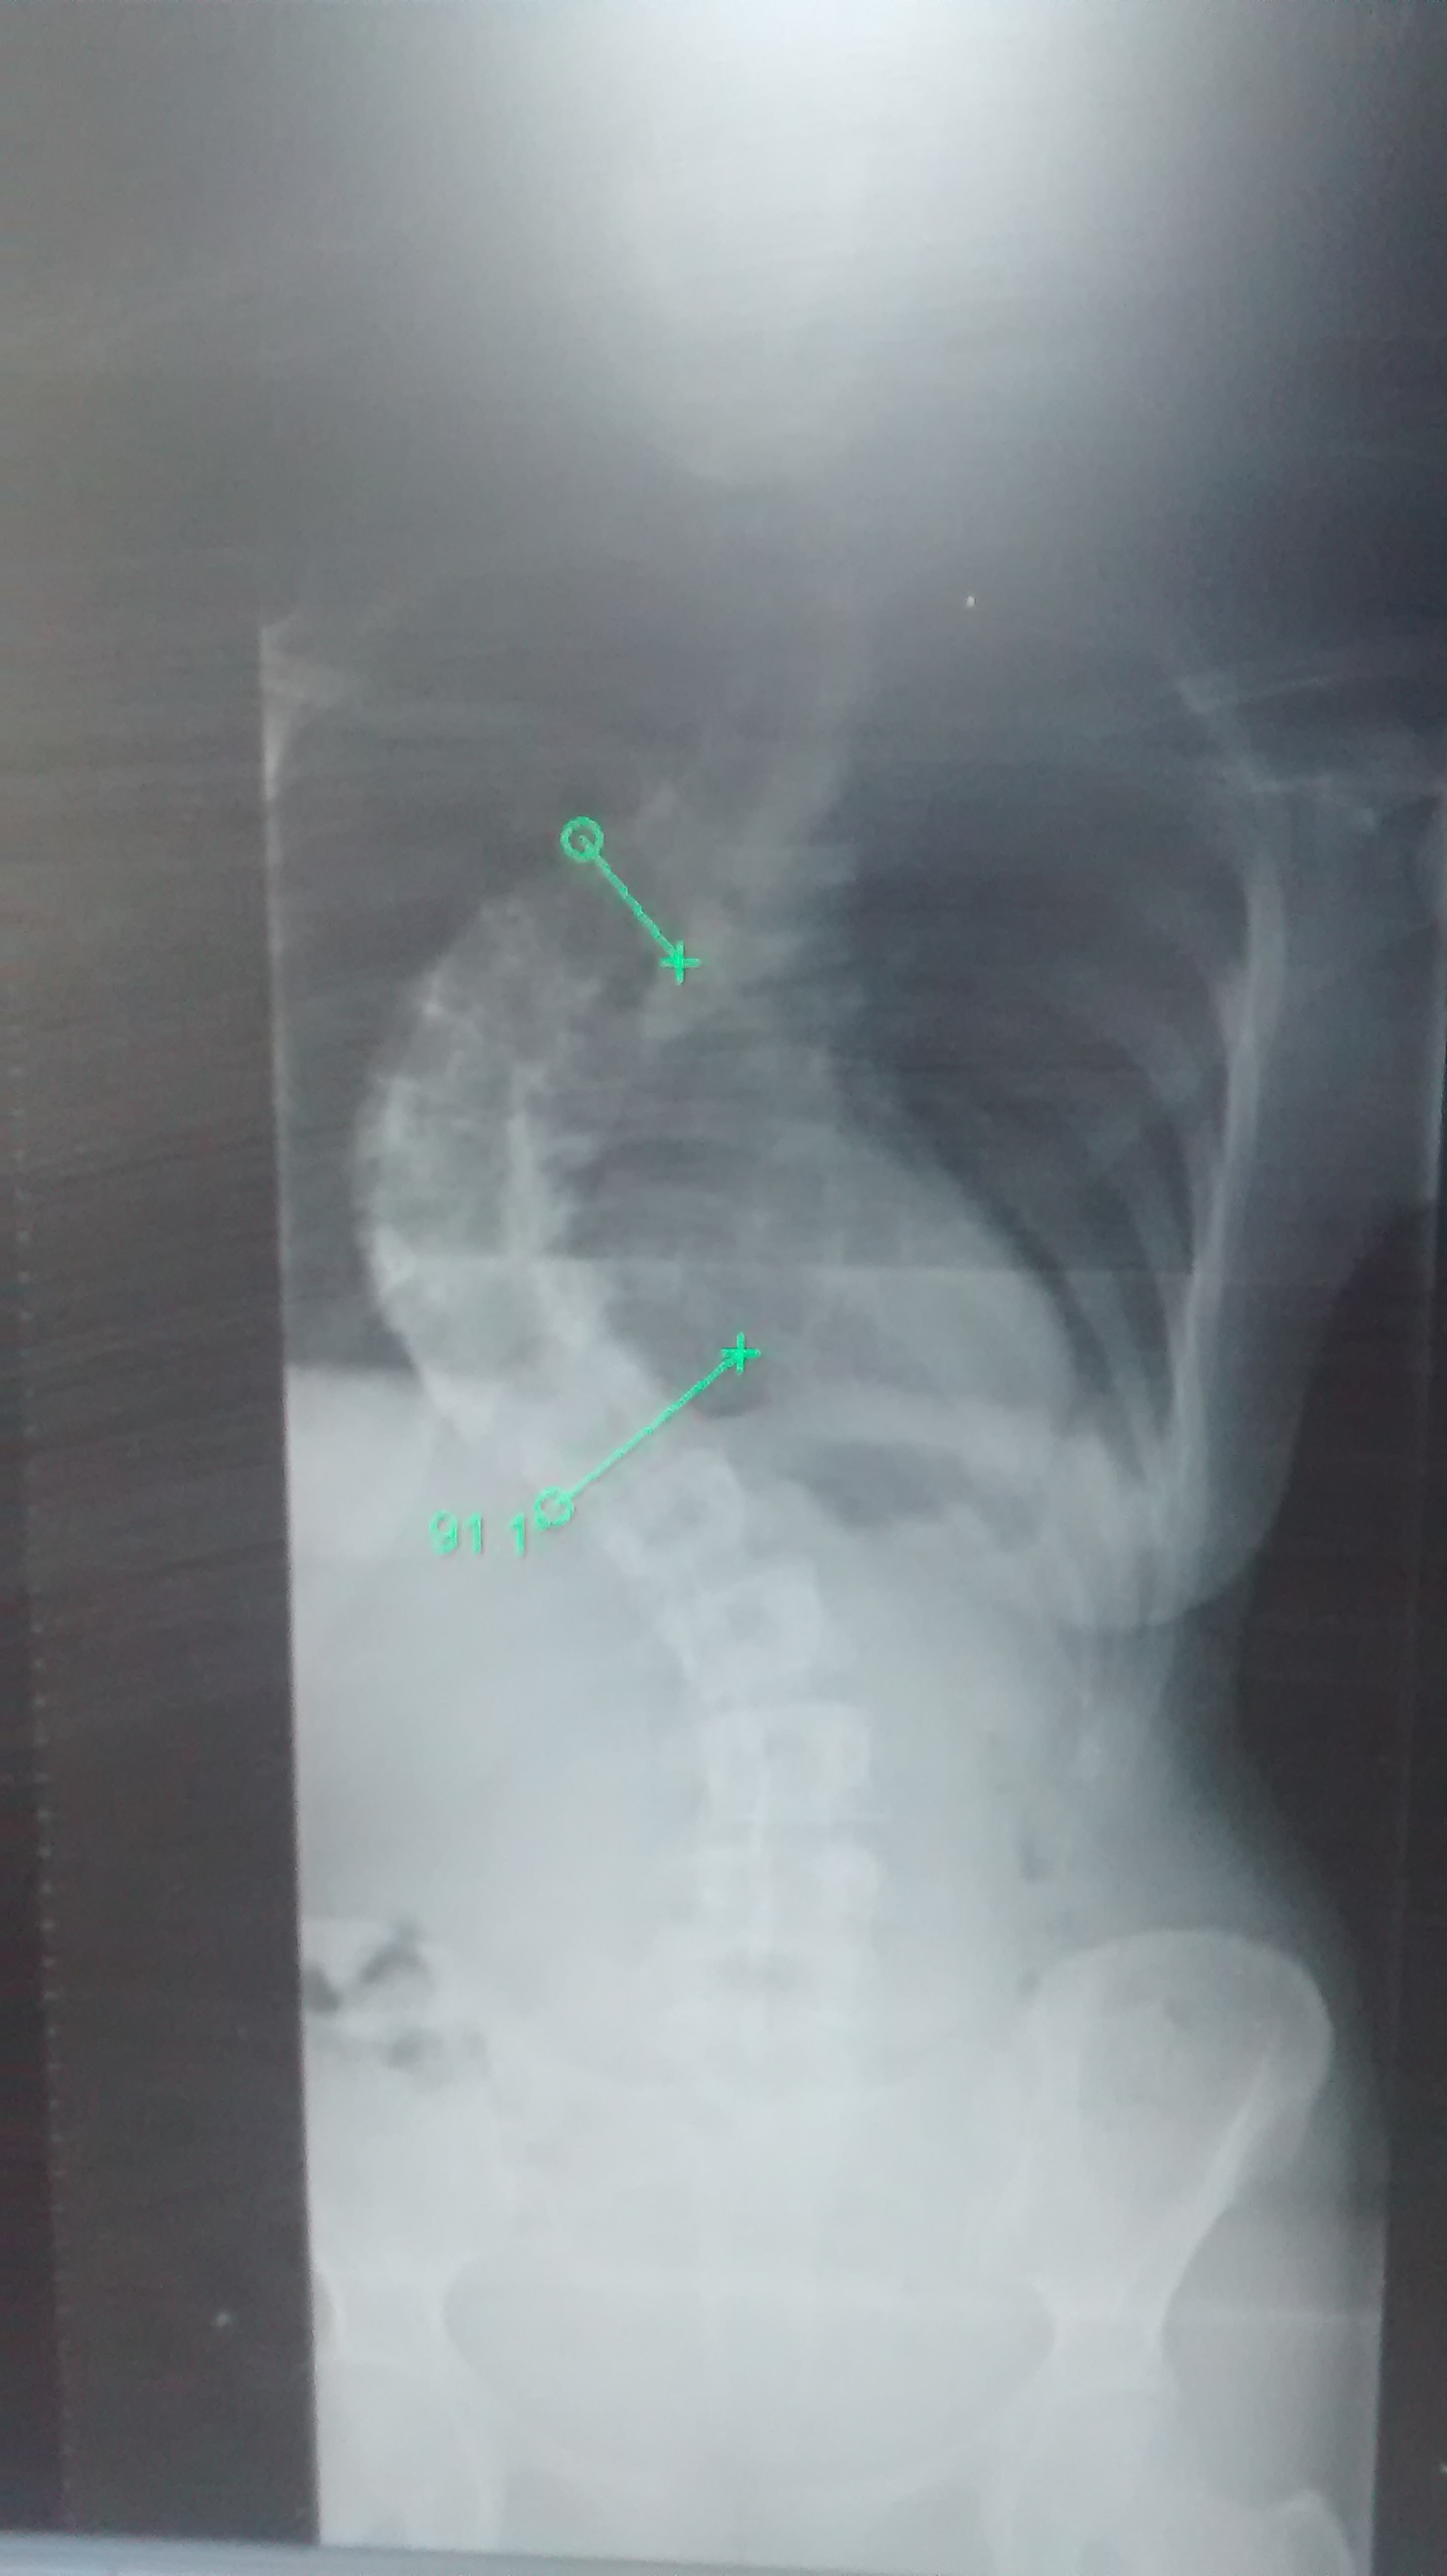

If you’ve found my website then I’m guessing you already know a little bit! Scoliosis is a sideways curve of the spine. There’s also some rotation of the vertebrae making scoliosis curves three dimensional. It’s this rotation that causes the raised area on one side (convex) and a compressed, hollow area on the opposite side (concave). In other words it creates a wonky body 🙂 A curve can be in any part of the spine and there may be more than one if you’re greedy! If the curve is in the thoracic spine (mid-back), it’s the spinal rotation that causes the ribs to twist and stretch outwards. Depending on the size and location of the curves in the spine; the shoulders, pelvis and hips may also be misaligned: for example one shoulder may be higher than the other.